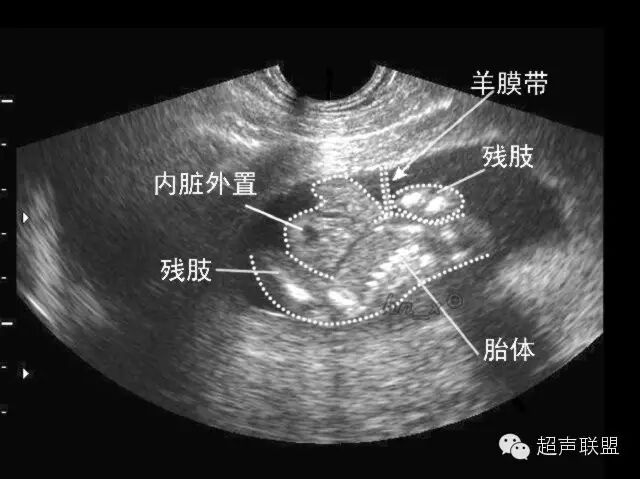

2、独眼畸形:独眼畸形是以面部中线单眼为特征的畸胎,有不同程度的眼部融合,完全独眼畸形表现为单一角膜、瞳孔、晶体,而没有任何成双的证据。在多数病例中,表现为单一眼眶内两个眼球的不同程度的融合。即使是完全的独眼畸形,上、下眼睑却有2个,视神经可表现为不同程度的重复。外鼻缺如或以一长鼻或象鼻的形式位于眼的上方。许多面部骨缺失,人中缺如。

3、头发育不全畸胎:此种畸形面部特征与独眼畸形极为相似,是独眼畸形的一种变种,但双眼及双眼眶不融合,极度眼距过近,鼻缺如或为长鼻,鼻骨、上颌骨、鼻中隔和鼻甲骨均缺如,泪骨和腭骨则融合,耳可有异常,位置过低。这种类型的异常亦只出现在无叶全前脑。